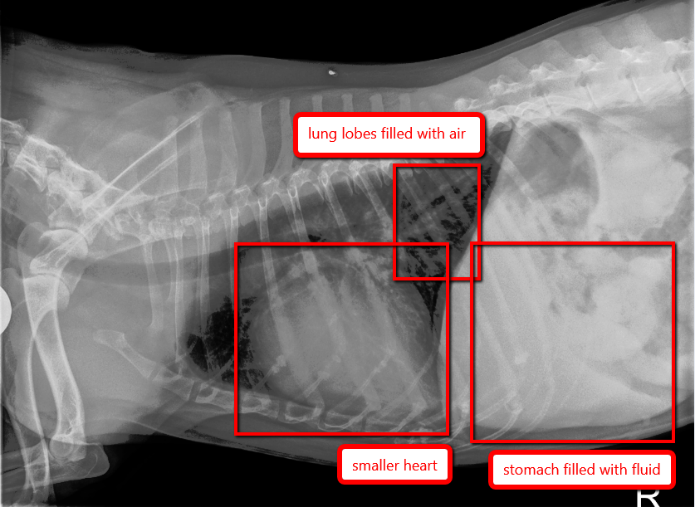

A radiograph taken one week after the first set shows that Lucy has responded very well to her congestive heart failure medications. She is also no longer coughing and struggling to breathe! Her heart silhouette is still large, but it has decreased somewhat. The previous whiteness (fluid) in her caudal lungs is significantly reduced; now, black air can be seen there. You can even see the normal blood vessels in her caudal lungs, whereas before, they were hidden by fluid. There is also much less air in her stomach. This radiograph represents a fantastic response to therapy!  And what kind of differences is her owner seeing? “Lucy is full of energy and enthusiasm! She loves to take walks, play in the snow, and go for car rides. She is very food-motivated; she especially loves bananas and homemade peanut butter treats! She is still afraid of strangers, but she deeply loves the people she knows and trusts,” says Katie.